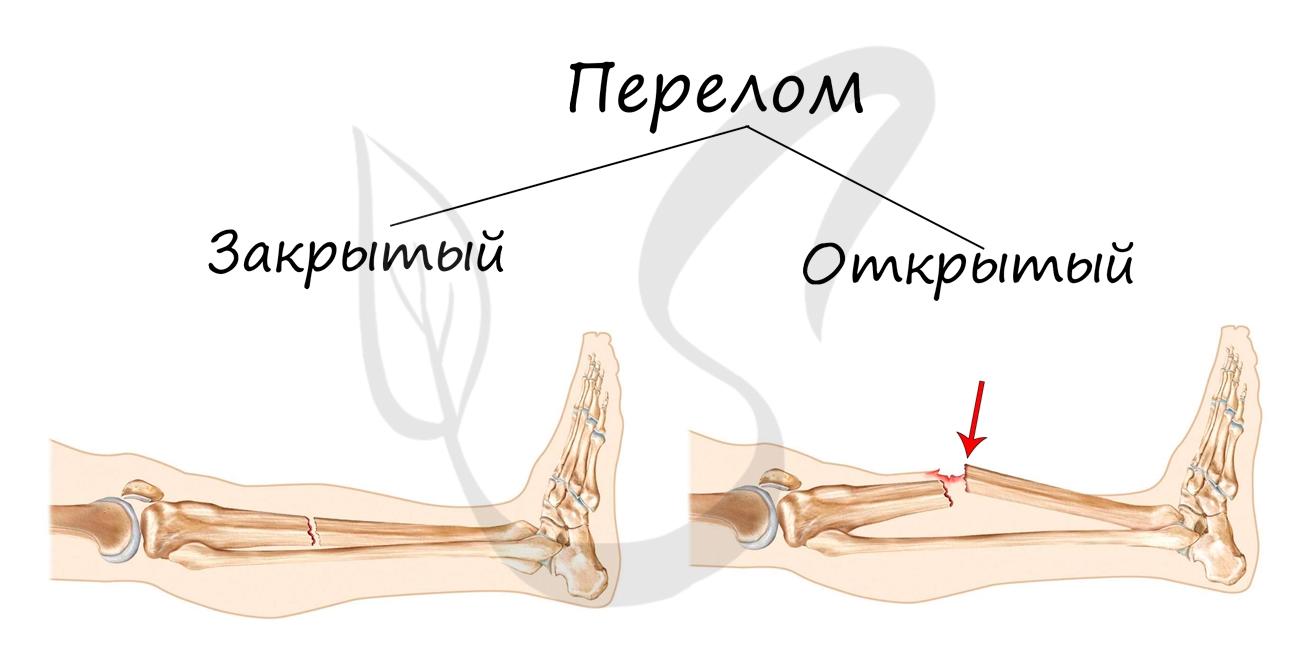

Переломы костей